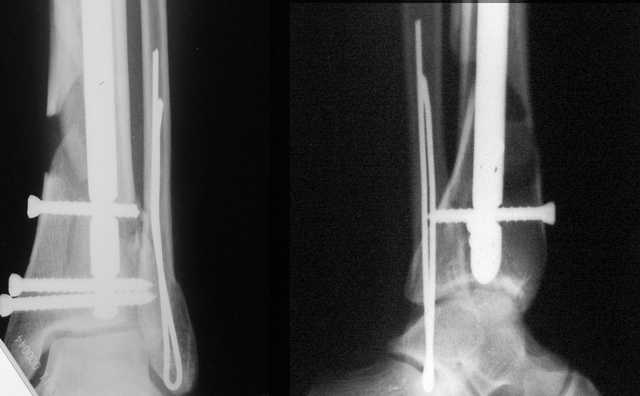

Я вот все в толк не возьму смысл отдельной фиксации малоберцовой кости пластинкой, если все равно будет аппарат с фиксацией стопы, т.е. возможностью провести спицы в пятку, таран, наружную лодыжку и еще черт-те куда. Остеосинтез пластинкой выглядит логичным в случае, когда наружная фиксация планируется как временная. Но тут-то аппарат будет окончательным фиксатором.

Еще, кстати, о фиксации лодыжки, если уж непременно хочется ее отдельно стабилизировать - при таком характере перелома замечательно должен сработать предложенный проф. Лазаревым с соратниками способ фиксации напряженной V-образной спицей. Опять же, открытая репозиция не нужна, мы делаем непрямую репозицию именно аппаратом. В приложении пример, там перелом малоберцовой куда менее поперечный, чем в данном случае, но все равно получилось закрыто без пластинки.

I can't realize why plate fibula separately if anyway external fixator including the foot is planned, i.e. one may insert wires to the talus, calcaneus, lateral malleolus and anywhere else. Plating looks reasonable if only temporary ex-fix is planned, but in the case it will be definitive.

A propos fibular fixation if one is eager to stabilize it separately. In the fracture pattern a way of closed fixation by V-shaped stressed wire (advanced by colleagues from Moscow, prof. Lazarev A.F. et al.) must be excellent. We use indirect closed reduction by the external fixator. Example attached, that fibular fracture is even more suitable for plating but the wire did the job.

I didn't perform stress tests, at least it prevents fibula against secondary displacement. Stressed 2 mm double wire is not so weak.

I used it only in two fibular cases recently. Colleagues from Moscow use the wires mostly for proximal humerus and even femoral neck.